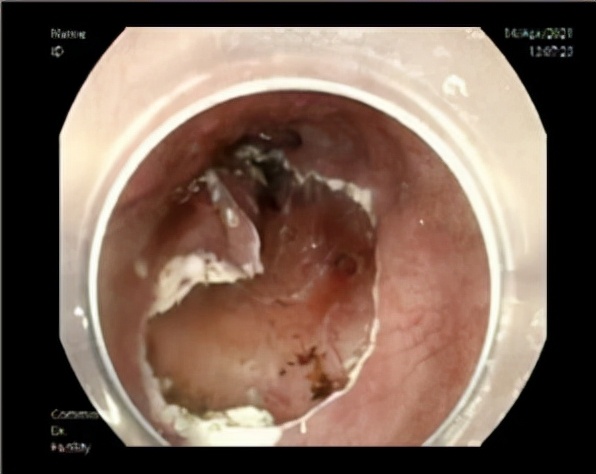

医生询问过后得知:男性,66岁,爱吃腌制食品,有抽烟、饮酒史,进食后胸骨后烧灼感,进食哽咽感,需高度怀疑食道病变,建议患者进行胃镜检查。胃镜提示食管距食道距门齿约38~40 cm处食管见一处表浅平坦型病变,表面色泽发红,黏膜粗糙,边界清晰,碘染色呈大片状不染区。活检病理结果:(食道)少量浅表黏膜,伴局灶高级别上皮内瘤变。医生向H先生交代疾病进展及治疗的必要性,患者住院行内镜下粘膜切除术。

术后病理提示:(食道)原位鳞状细胞癌(3.0*1.8*0.2 cm),未见脉管癌栓及神经侵犯,水平切缘及基底未见癌组织。非常幸运的黄先生其食管早癌治愈了。